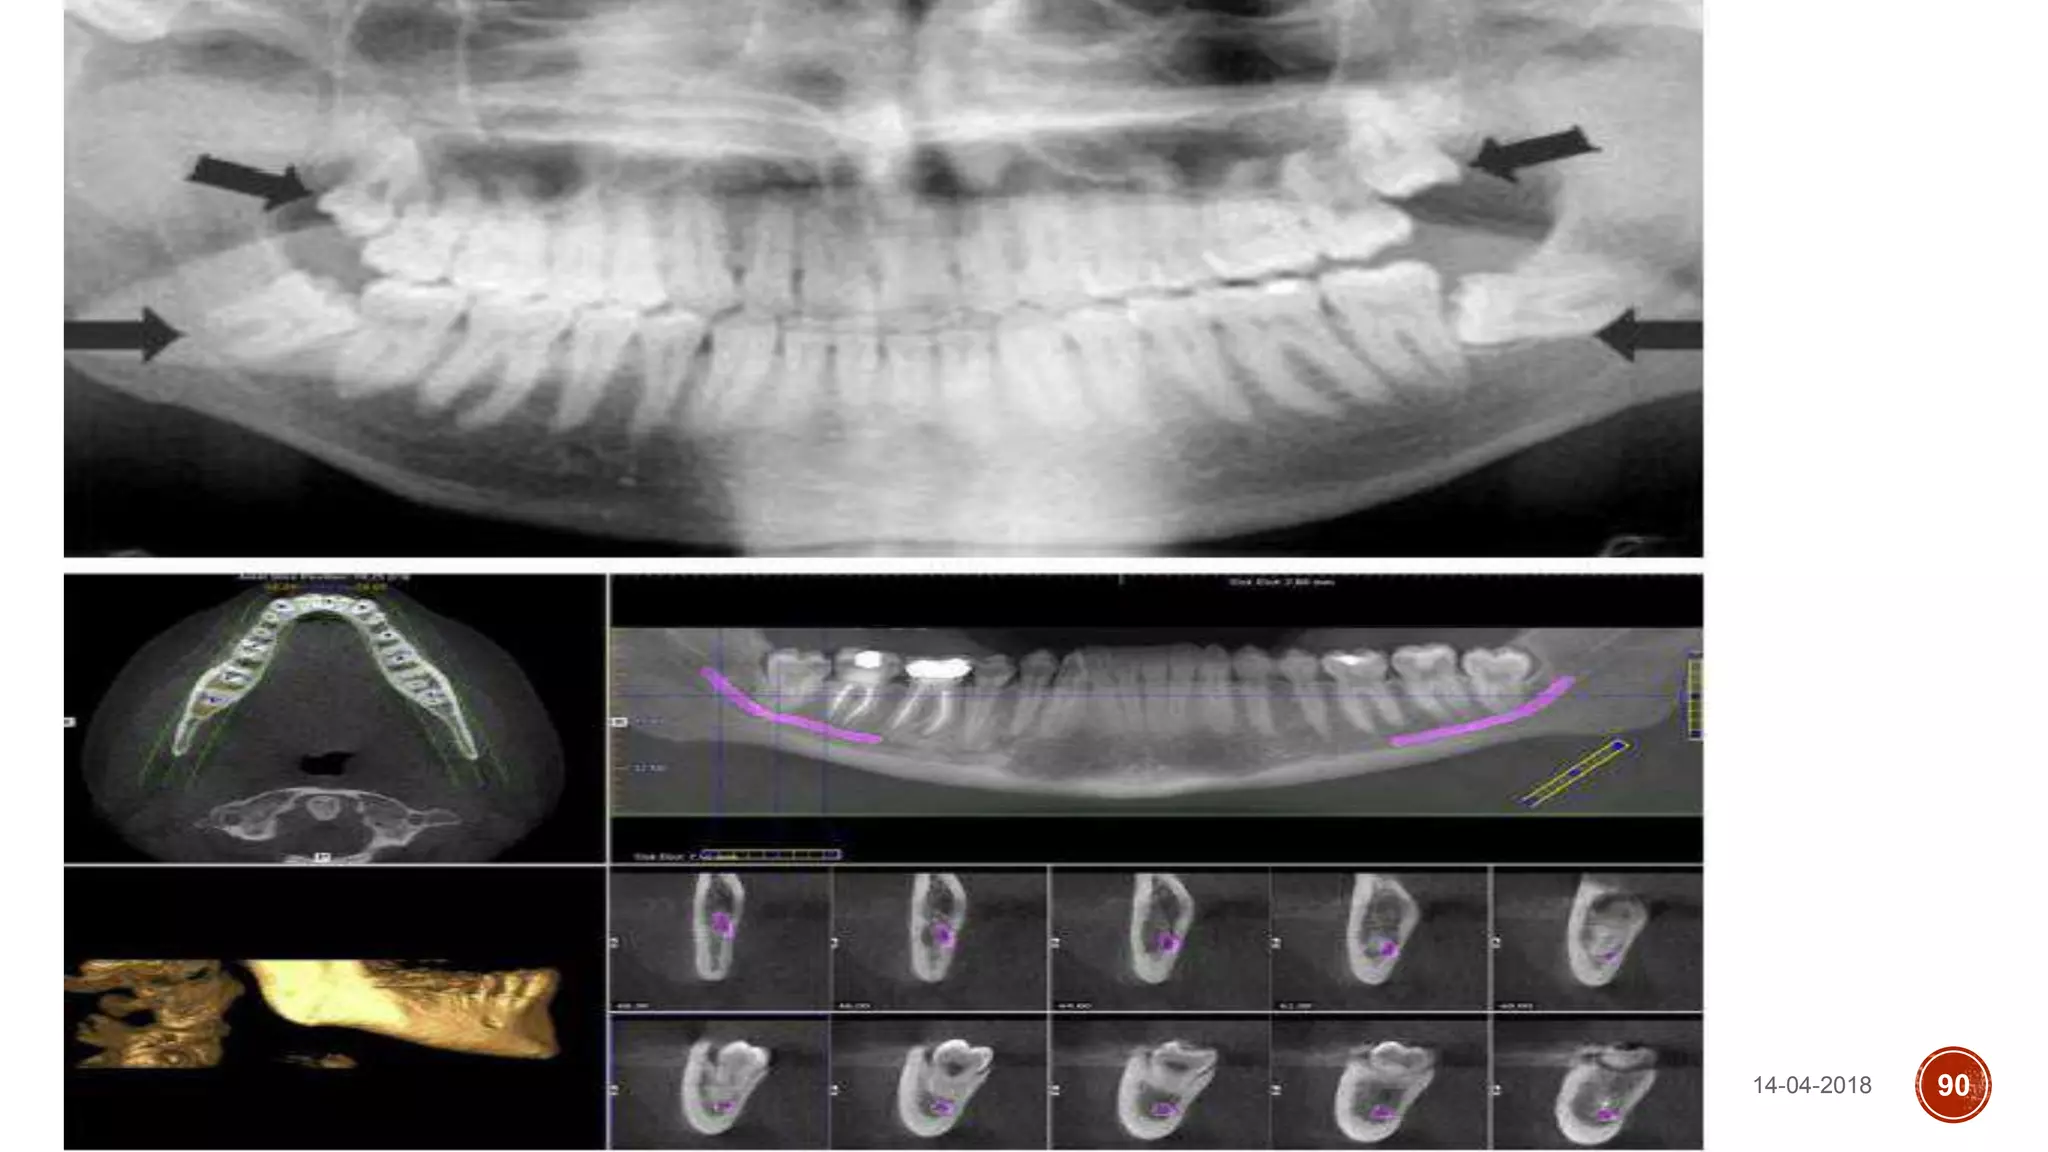

CONE BEAM COMPUTED TOMOGRAPHY

(CBCT)

CT-scan

Superior in showing tooth and root

Shape, crown/root relationship,

Tooth inclination and gives exact idea

Of the proximity of IAN and canal to the

Roots.

14-04-2018 90